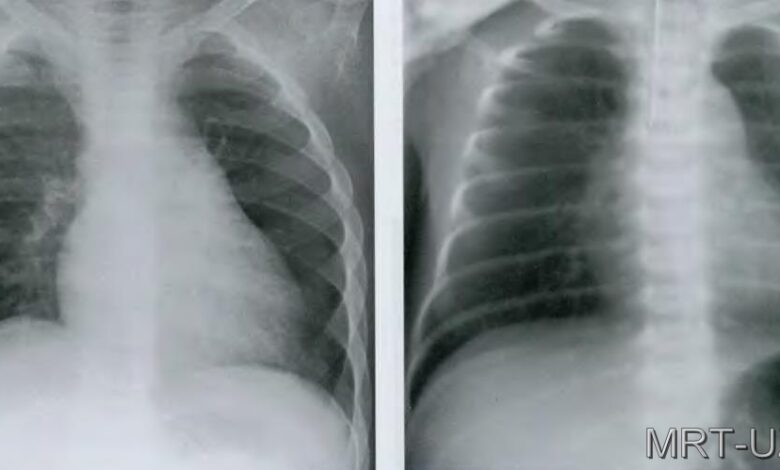

Рентген легких в двух проекциях

Два основных типа проекций: прямая (передне-задня) и боковая (боковая).

Прямая (передне-задня) проекция

В прямой проекции рентгеновский луч проходит через переднюю поверхность тела пациента и попадает на пленку, расположенную сзади. Этот метод позволяет оценить состояние всех отделов легких и диафрагмы.

Боковая (боковая) проекция

При боковой проекции рентгеновский луч проходит через боковую поверхность тела пациента. Этот метод позволяет получить информацию о задних отделах легких, а также о состоянии позвоночника и ребер.